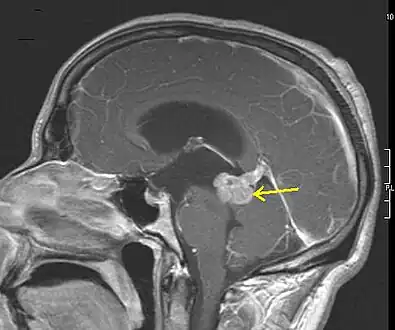

Low grade astrocytoma of the midbrain (lamina tecti), sagittal T1-weighted magnetic resonance imaging after contrast medium administration: The tumor is marked with an arrow. The CSF spaces in front of the tumor are expanded due to compression-induced hydrocephalus internus.

Low grade astrocytoma of the midbrain (lamina tecti), sagittal T1-weighted magnetic resonance imaging after contrast medium administration: The tumor is marked with an arrow. The CSF spaces in front of the tumor are expanded due to compression-induced hydrocephalus internus. A pathological specimen of a gemistocytic astrocytoma